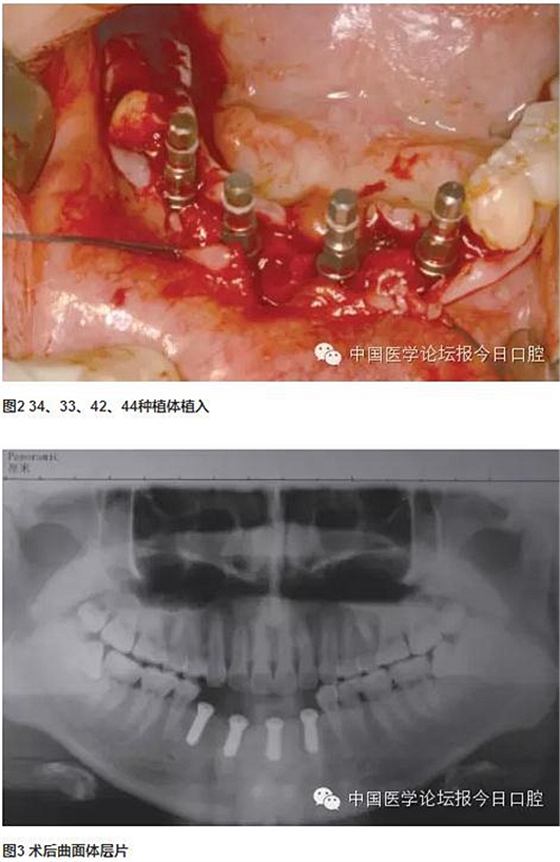

分別于下頜左側(cè)尖牙、下頜左側(cè)中切牙、下頜右側(cè)側(cè)切牙、下頜右側(cè)第一前磨牙位點植入4顆長度為10mm的常規(guī)頸種植體,3個月后取模制作研究蠟型,可見種植體開口方向均在舌側(cè),較適合制作螺絲固位修復體。兩次法取模,已釋放材料收縮應(yīng)力對取模的準確性產(chǎn)生的影響,確保石膏模型上種植體位置準確。

技工室制作純鈦支架,聚合瓷修復牙齒和牙齦形態(tài),患者口內(nèi)試戴,只將一個種植體的固定螺絲加力,拍片可見其余3顆種植體均實現(xiàn)被動就位,然后將4顆種植體固定螺絲加力,封口(圖2~圖10)。